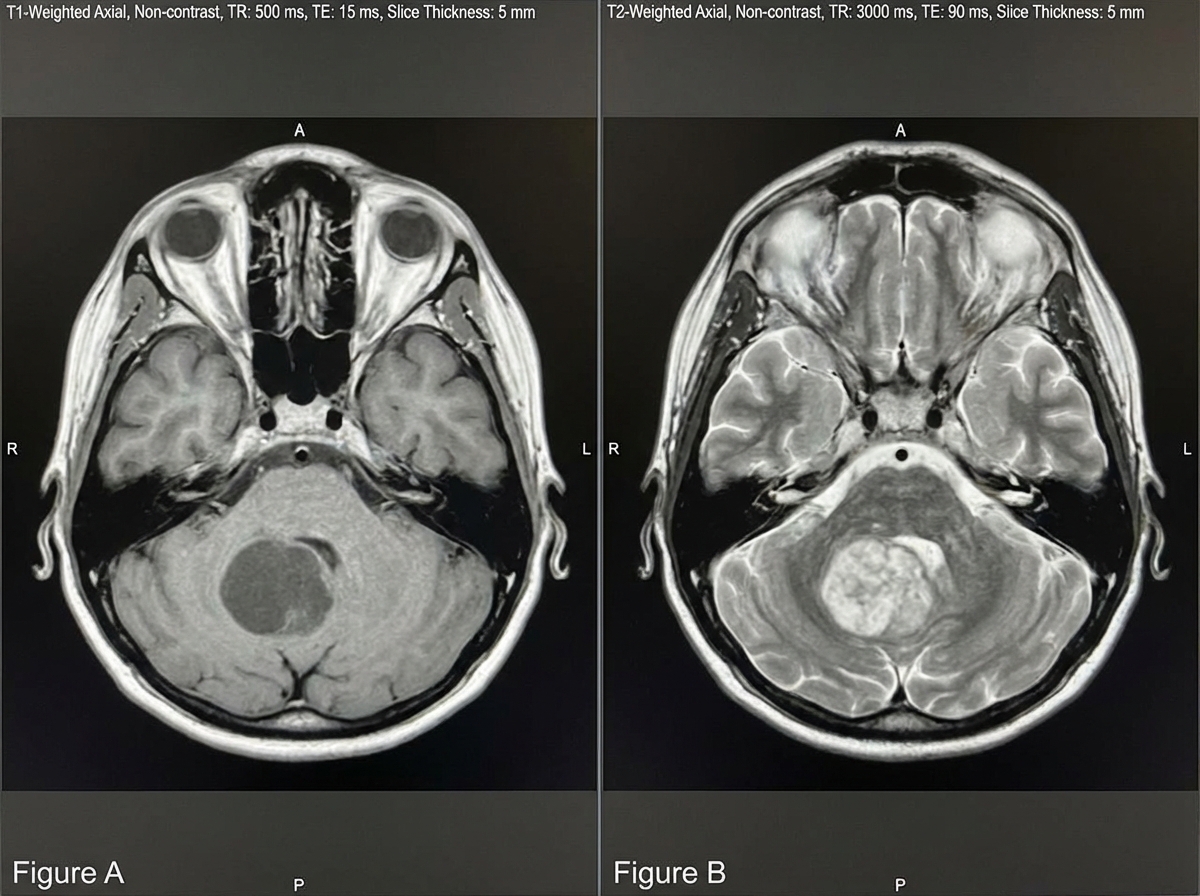

A 6-year-old boy is brought in by his mother to his pediatrician for headache and nausea. His headaches began approximately 3 weeks ago and occur in the morning. Throughout the 3 weeks, his nausea has progressively worsened, and he had 2 episodes of emesis 1 day ago. On physical exam, cranial nerves are grossly intact, and his visual field is intact. The patient has a broad-based gait and difficulty with heel-to-toe walking, as well as head titubation. Fundoscopy demonstrates papilledema. A T1 and T2 MRI of the brain is demonstrated in Figures A and B, respectively. Which of the following is most likely the diagnosis?